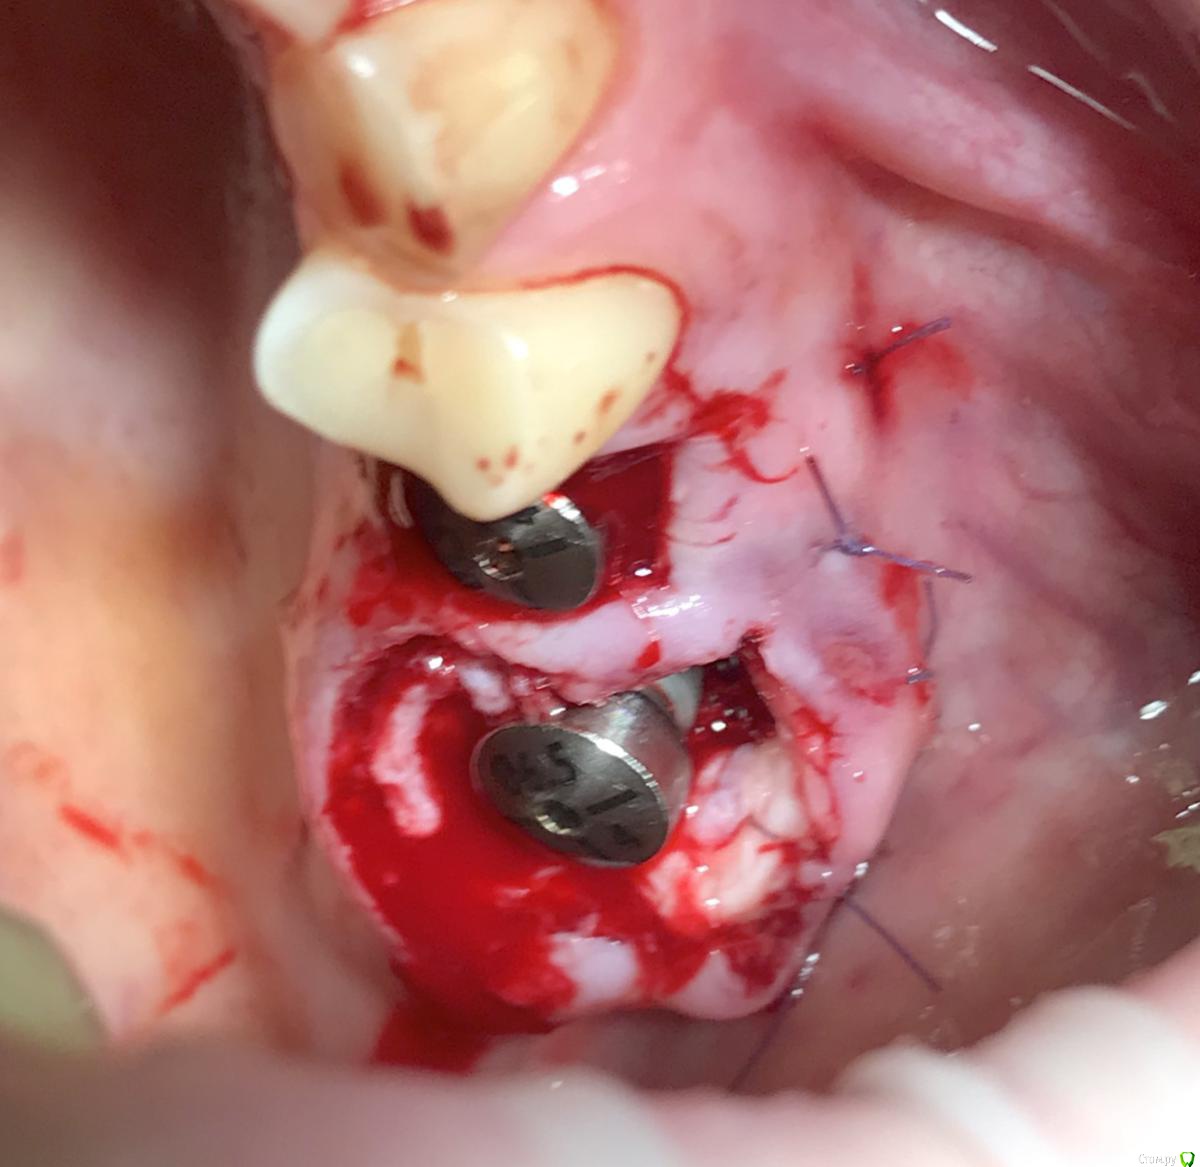

колесников Опубликовано 9 мая, 2017 Автор Поделиться Опубликовано 9 мая, 2017 Да,"приберечь " это про низ. Бугор берётся расщеплённый,не полностью, хорошо регенерирует . Через 4 недели можно брать снова. Травма у нас местно есть в любом случае,кератинизированая расщеплённая десна регенерирует очень хорошо и малоболезненно. Как пример фото разместил :в первом случае со "змейки " я снял швы через неделю и простился,во втором ,где свободный лоскут,остатки его убрал через 3 недели и ещё неделя наблюдений.На фото расщеплённый бугор. На последнем -с выделенным сст. Ссылка на комментарий

колесников Опубликовано 5 июля, 2019 Автор Поделиться Опубликовано 5 июля, 2019 Ещё раз о ретировалось лоскуте . Из ретромолярной зоны на н/ч перекинут Вестибулярно к 7ке и с неба перекинут Вестибулярно уже для верхней 7ки. Оба случая значительный дефект вестибулярной стенки,одномоментная имплантация,грануляции. Получается хороший стабильный и плотный каркас. 1 зона. 1 Ссылка на комментарий

колесников Опубликовано 3 августа, 2019 Автор Поделиться Опубликовано 3 августа, 2019 27ой закрыт «бугром на ножке»,вид через неделю. Всем рекомендую 1 Ссылка на комментарий

колесников Опубликовано 8 августа, 2019 Автор Поделиться Опубликовано 8 августа, 2019 Ещё о перемещении бугра 2 Ссылка на комментарий